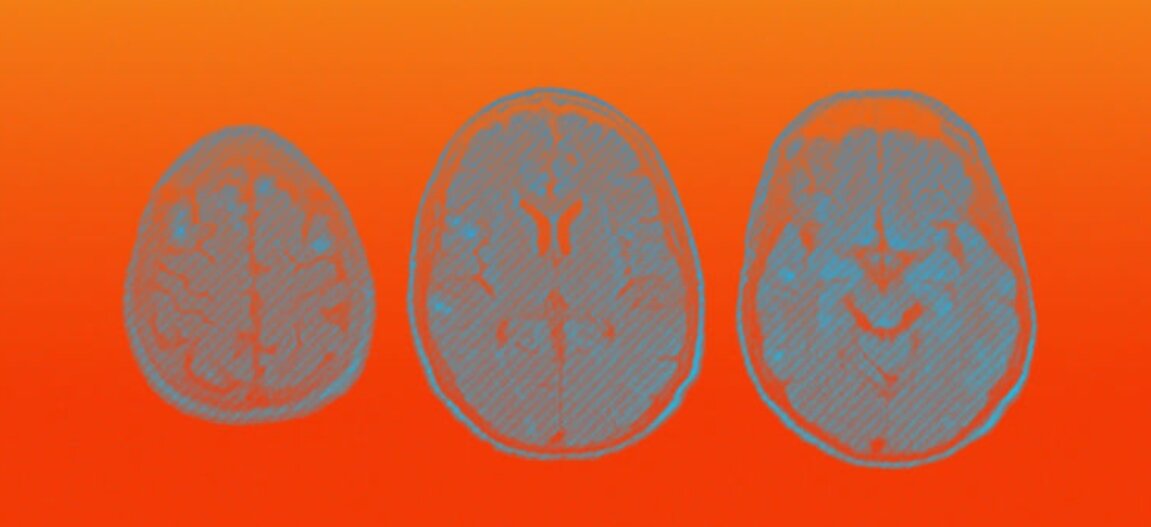

В новом исследовательском документе , подготовленном группой исследователей из Института неврологии Университетского колледжа Лондона (UCL) и опубликованном сегодня во влиятельном журнале Brain , были исследованы 43 пациента с COVID-19, которые испытали широкий спектр заболеваний головного мозга, по-видимому, в результате коронавирус.

К ним относятся инсульты, а также поразительно высокий уровень острого диссеминированного энцефаломиелита (ADEM), редкого неврологического расстройства, характеризующегося распространенным воспалением в головном мозге.

Восемь пациентов перенесли инсульт, в то время как еще восемь имели повреждение периферических нервов, диагностированное как синдром Гиллиана-Барре, состояние, при котором собственная иммунная система организма атакует нервы.